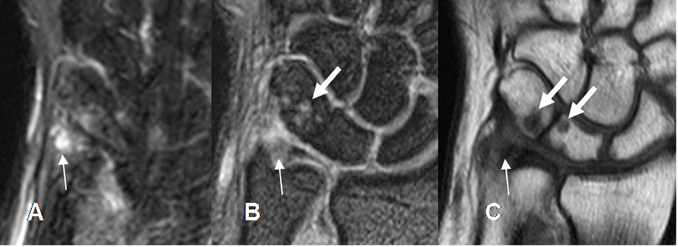

Fig 79 A. Ruptura del complejo del FCT.

A: RM coronal en T2 y B: RM coronal en T1. Solución de continuidad del cartílago, a nivel central por lesión tipo 1A.

Fig 79 B. Ruptura del complejo del FCT.

A: RM coronal en T1. Alteración en la señal del FCT, sobre su inserción ulnar.

B: RM coronal en GE. Solución de continuidad en la inserción ulnar del FCT, por ruptura tipo 1B. Existe líquido en la articulación radioulnar distal. (Flecha gruesa).

Fig 79 C. Ruptura del complejo del FCT.

A: RM coronal en T1 y B: RM coronal en GE. Líquido en la articulación radioulnar distal, como signo de ruptura del FCT (Flechas delgadas). Hay ruptura del menisco en la inserción radial por lesión tipo 1D. (Flecha gruesa).